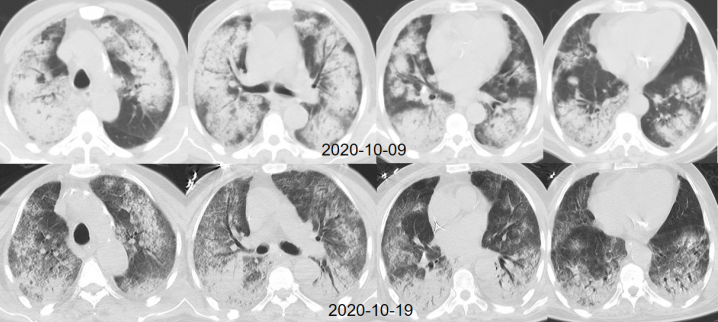

影像改变

患者胸部X线片可见渗出较前有所吸收(图3)

图3  患者影像学改善情况

上机后1周,于2020年10月17日成功撤离ECMO。复查胸部CT可见渗出实变影较前吸收,影像学改善(图4)

图片

图4  患者撤离ECMO后复查胸部CT